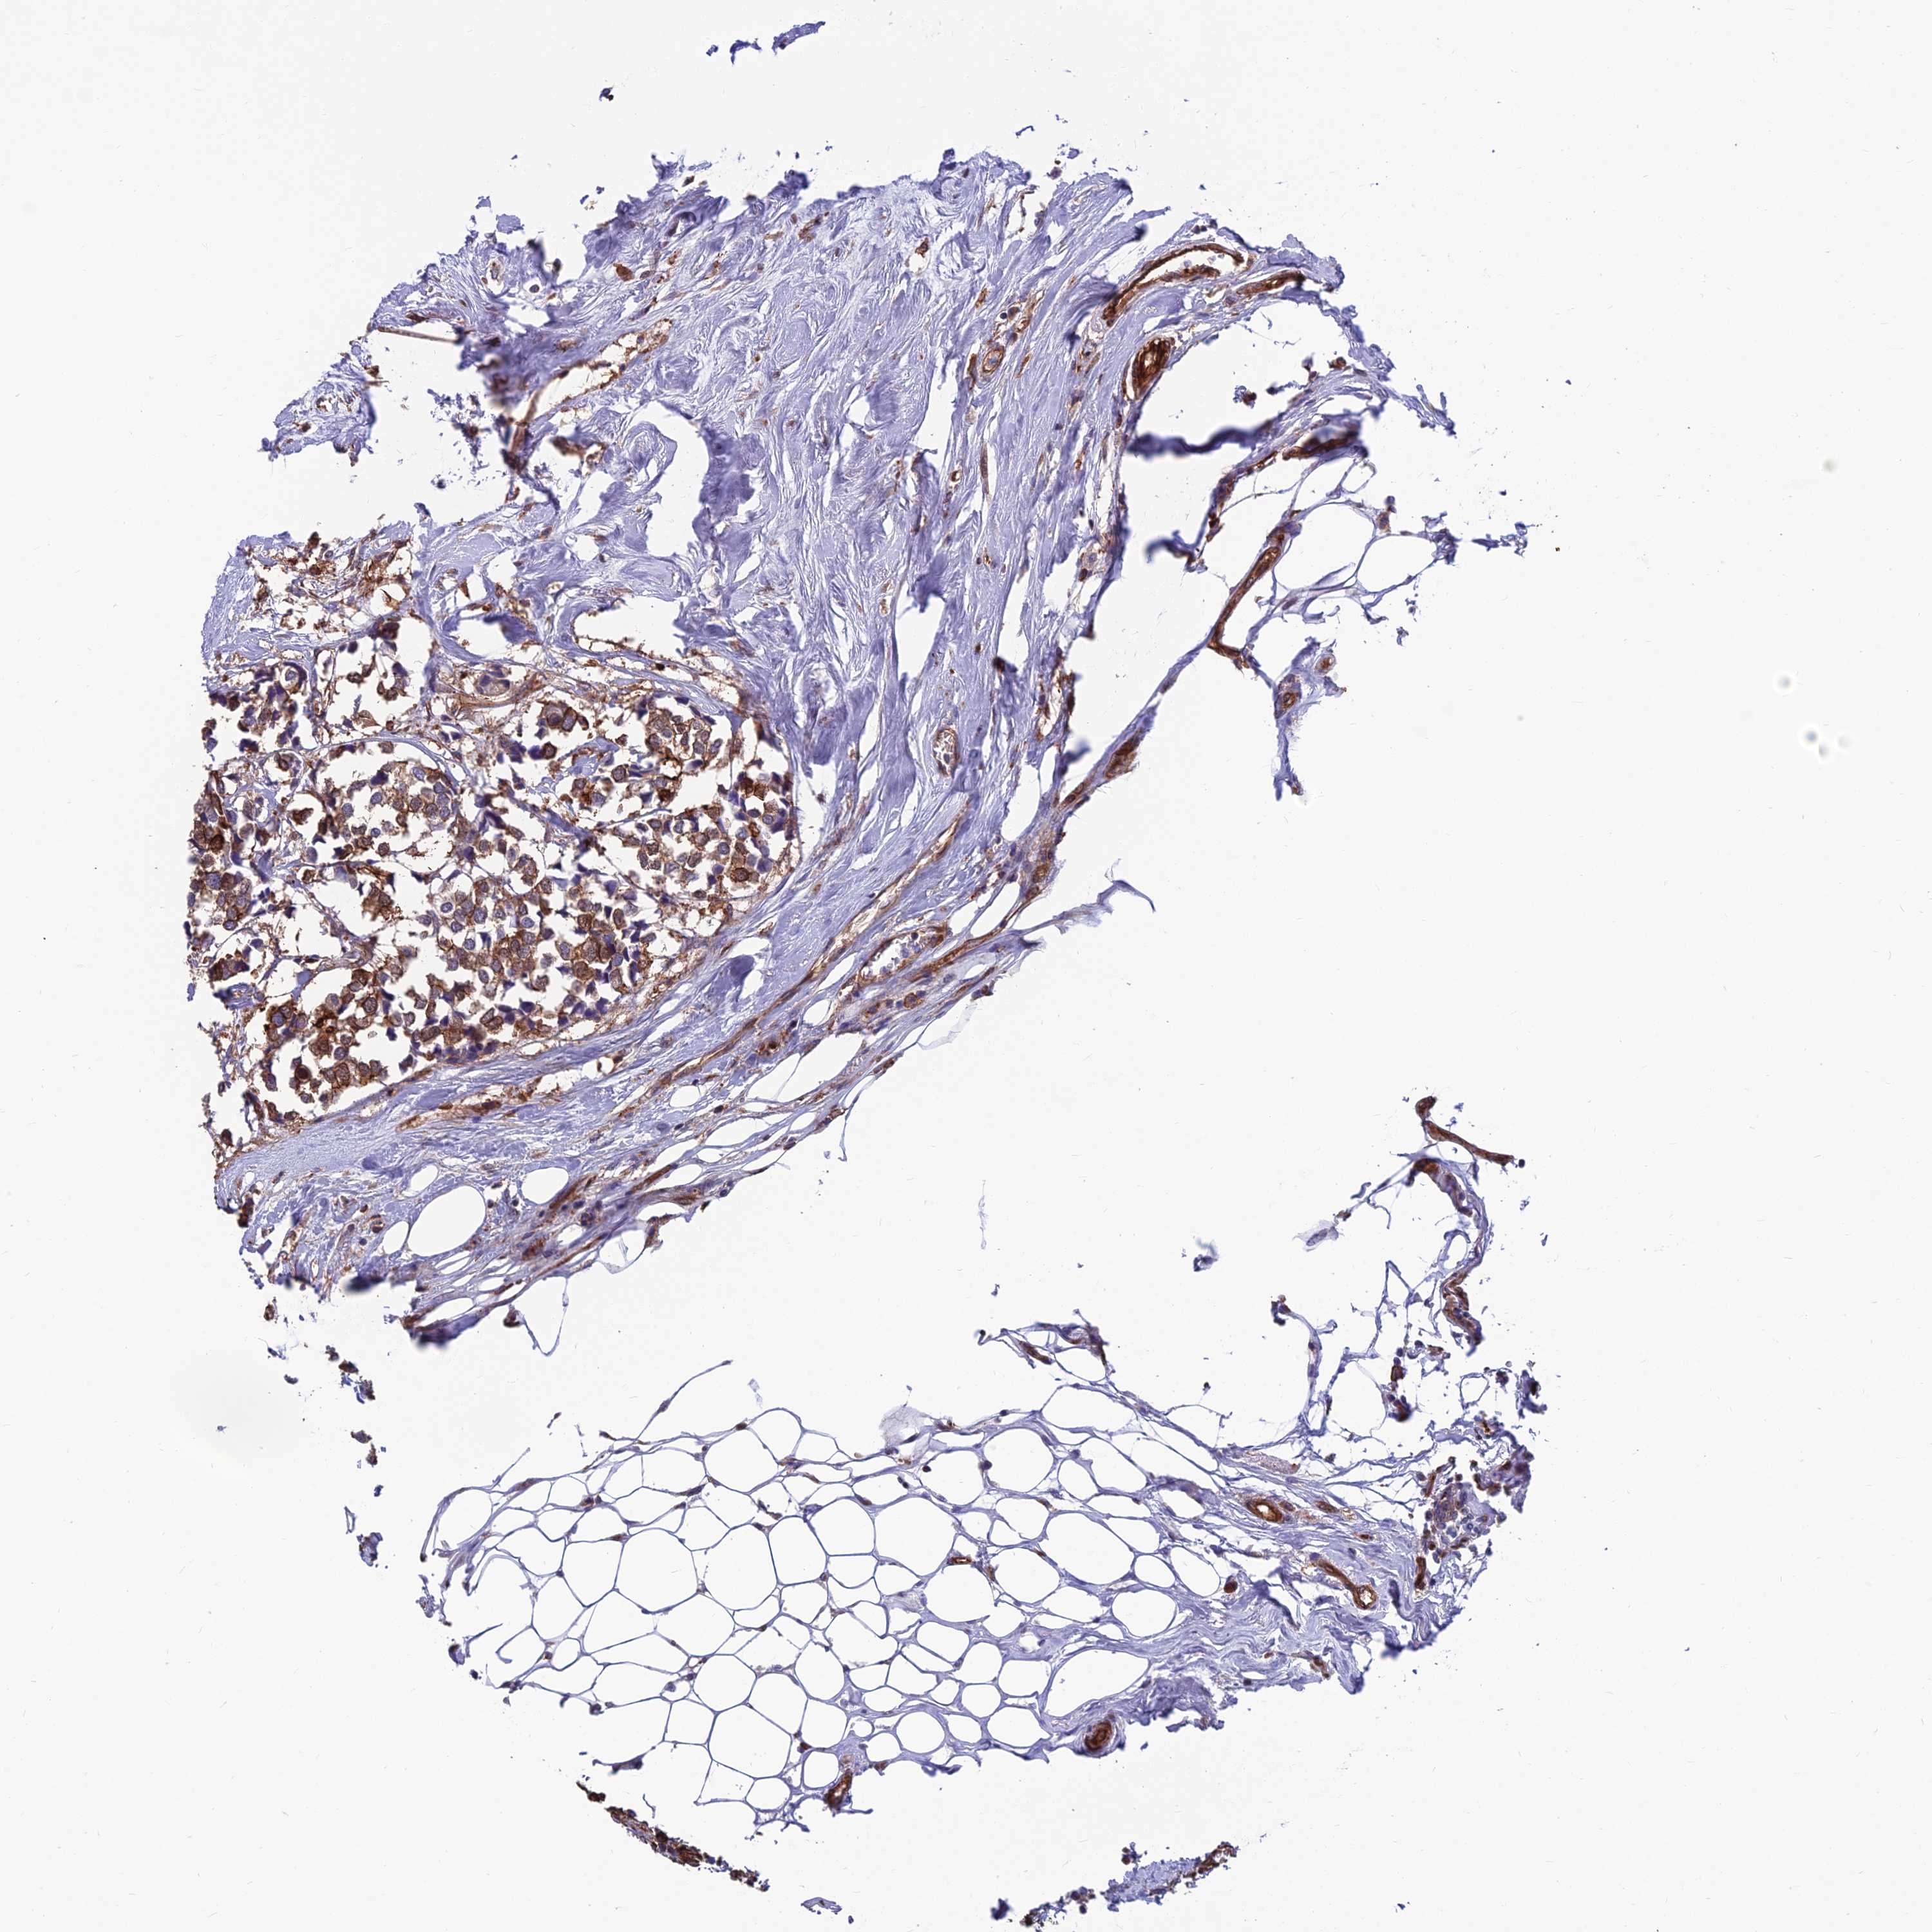

CANCER BREAST CANCER Show tissue menu

BRCA TCGA BRCA VALIDATION PROTEIN EXPRESSION